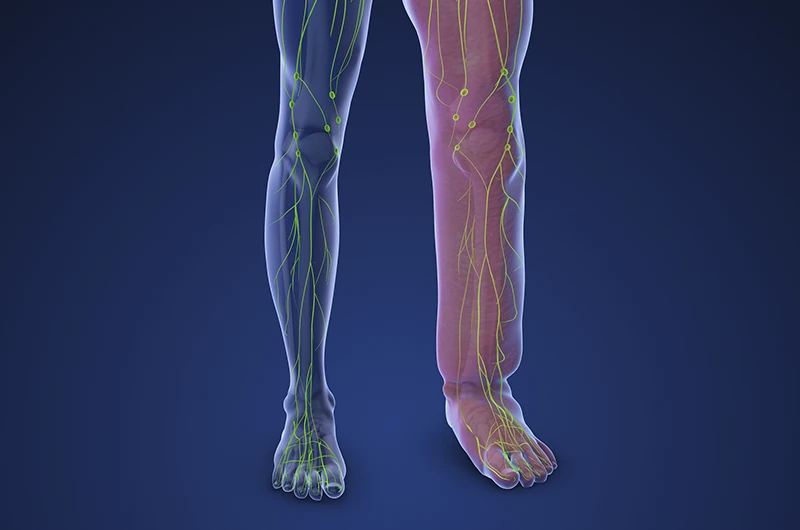

Lipedema

Meu compromisso é oferecer um atendimento vascular completo, humano e indolor, com foco em tratar queixas que impactam diretamente a qualidade de vida, como o Lipedema.